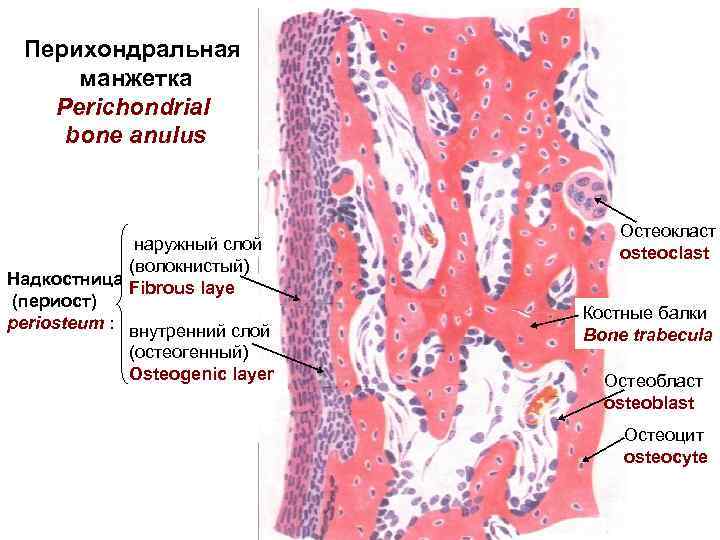

Структура грубоволокнистой костной ткани: наглядные примеры